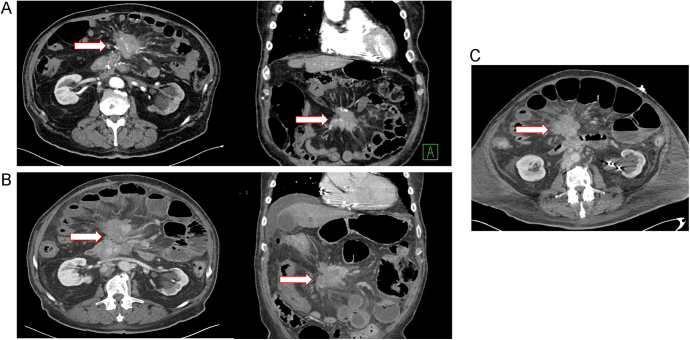

Results: Among the cases reviewed, we identified three patients who developed bowel ischemia/perforation shortly after their initial treatment with 177Lu-DOTATATE. All patients had metastatic small bowel NET with prominent mesenteric mass encasing/obstructing the mesenteric vessels and preexisting symptoms of postprandial abdominal pain.

Conclusion: Acute bowel ischemia may be a rare complication of PRRT in patients with mesenteric arterial or venous obstruction from mesenteric metastasis.